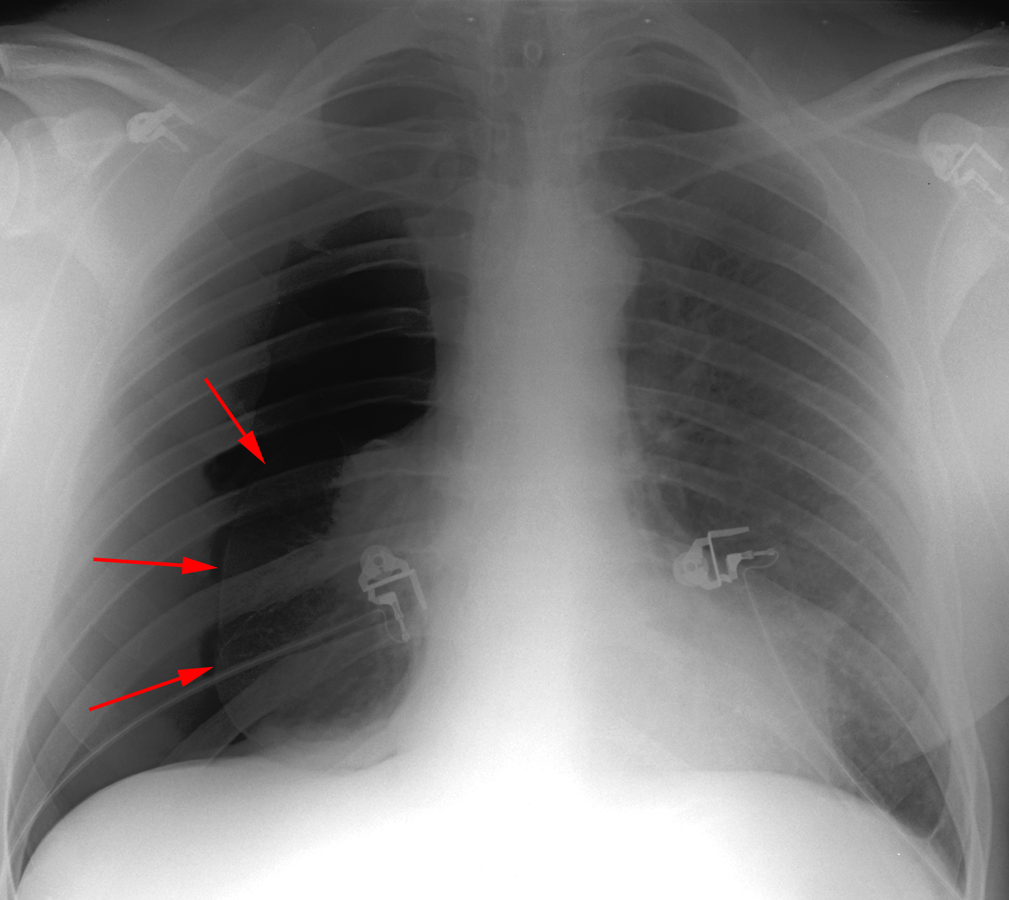

Pneumothorax

Defined as air inside the thoracic cavity but outside the lung (pleural space).

On CXR, a PTX appears as air without lung markings in the least dependant part of the chest. Generally, the air is found peripheral to the white line of the pleura. In an upright film this is most likely seen in the apices. A PTX is best demonstrated by an expiration film. It can be difficult to see when the patient is in a supine position. In this position, air rises to the medial aspect of the lung and may be seen as a lucency along the mediastinum. It may also collect in the inferior sulci causing a deep sulcus sign.

Apicolateral pneumothorax

Appears as a thin, white pleural line with no lung markings beyond. The presence of lung markings beyond this line, though, does not exclude pneumothorax. This is especially true in the patient with parenchymal disease which may alter the compliance of affected lobes, making their collapse more difficult to detect radiographically. Parenchymal disease may also make visualization of the pleural line more difficult or impossible.